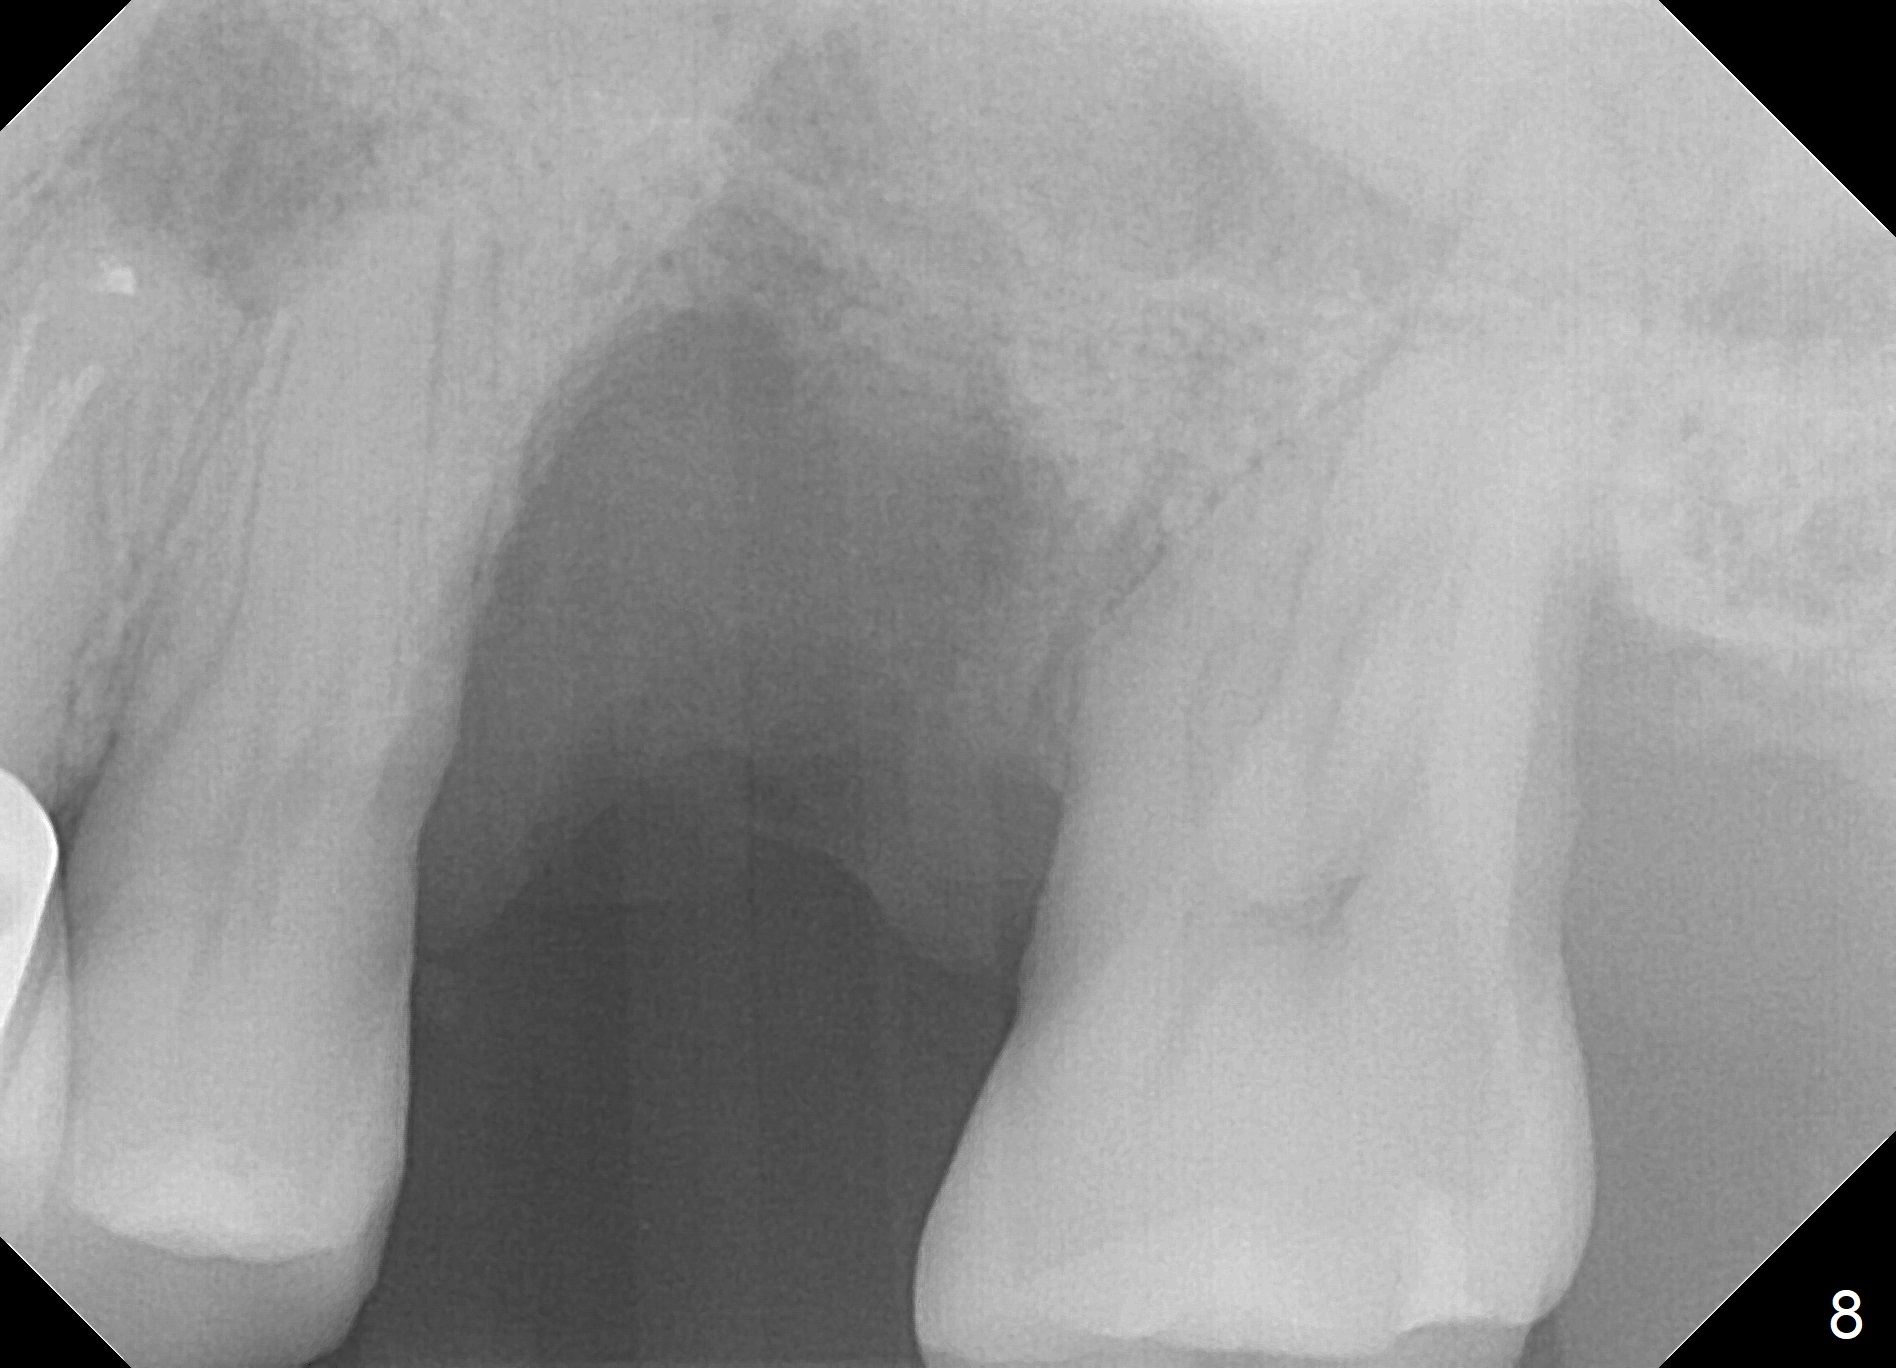

When the tooth #14 is extracted, the buccal plate is lost, while the apex of the palatal socket is perforated.  The palatal slope of the septum appears to be a suitable site for osteotomy, but the depth seems to be 2 mm.  After sequential osteotomy until 5.3 mm with drills, a 5.9 mm SM tap obtains stability (Fig.2).  A 5.9x8 mmm implant is placed with barely sufficient stability after 1 piece of PRF membrane and VeraGraft (Fig.2-4).  The implant rotates and dislodges when an abutment is being placed.  Neither do 6-8x17 mm Tatum taps achieve primary stability.  Socket preservation is performed, followed by periodontal dressing (Fig.5).  Primary stability might have been obtained if a smaller IBS implant with fins were placed in the palatal socket.  The periodontal dressing has dislodged 1 week postop; the socket appears healing (Fig.6,7).  Bone graft seems to be minimal or bone density of the graft is low (Fig.8).  The socket heals with a wide ridge 2 months post socket preservation, but the tooth #15 seems to be buccal (Fig.9) and mesial (Fig.10) shift.  After use of Magic Split and Expanders (until 3.8 mm for 13 mm), try 5 mm dummy implant (Fig.11).  If 6 mm one fails to achieve stability substantially, switch to 7 mm Tatum tapered tap provided there is enough mesiodistal space (use 8 mm implant positioner to gauze the space beforehand (preop)).  Consider using Vanilla (not Vera) Graft to fill in the gap between implant and osteotomy.  When primary stability is obtained, place a nonfunctional provisional to prevent further shifting (Fig.11 white outline).  After osteointegration, use the provisional (reline and separator) to distalize the tooth #15.